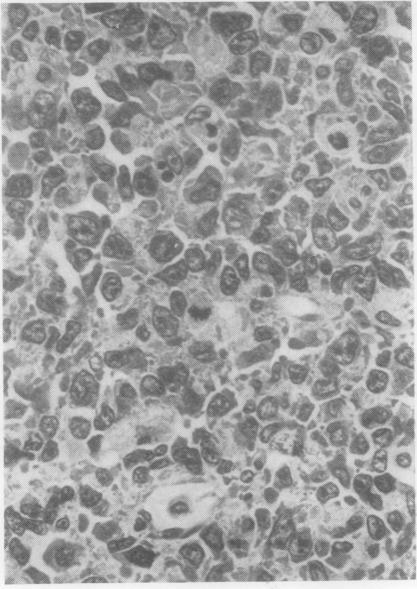

The clinical and pathological findings of a case of systemic angioendotheliomatosis are presented. The previously published cases of this disease are analysed. The present case is only the third to show clear evidence of metastasis.

本文报告了一例系统性血管内皮瘤病的临床及病理表现。对该疾病既往已发表的病例进行了分析。本病例是第三例有明确转移证据的病例。